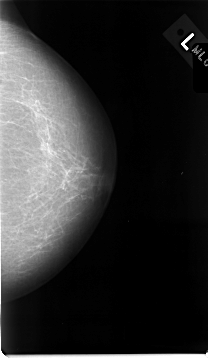

C_0014_1.LEFT_MLO

C_0014_1.LEFT_CC

LEFT_MLO LINES 4632 PIXELS_PER_LINE 2824 BITS_PER_PIXEL 12 RESOLUTION 50 NON_OVERLAY